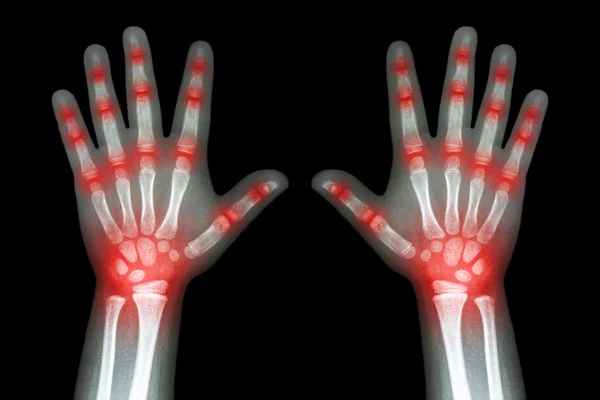

Rheumatoid Arthritis X Ray : The rheumatoid community on reddit.. Severe rheumatoid arthritis of the wrist and hand. Rheumatoid arthritis (present for >10 years). Rheumatoid arthritis can be difficult to diagnose because many conditions cause joint stiffness and inflammation and there's no definitive test for the condition. Rheumatoid arthritis (ra) is a chronic autoimmune multisystemic inflammatory disease that affects many organs but predominantly attacks the synovial tissues and joints. Rheumatoid arthritis manifests as a symmetrical arthritis, most commonly affecting the hands.

It typically results in warm, swollen, and painful joints. Rheumatoid arthritis can be difficult to diagnose in its early stages because the early signs and symptoms mimic those of many other diseases. The 2010 rheumatoid arthritis classification criteria help doctors diagnose rheumatoid arthritis. Rheumatoid arthritis (ra) is a chronic systemic inflammatory disease of unknown cause. The ulnar styloid is destroyed with the rest of the distal ulna (white arrow), there is destruction of the carpal bones (yellow arrow) and there is dislocation of the 1st metacarpal on the destroyed trapezium.

Intake of gold preparations (rheumatoid arthritis), lithium, some antibiotics, narcotics (heroin). Rheumatoid arthritis is considered an indication for resurfacing of the patella during total knee arthroplasty. The ulnar styloid is destroyed with the rest of the distal ulna (white arrow), there is destruction of the carpal bones (yellow arrow) and there is dislocation of the 1st metacarpal on the destroyed trapezium. Rheumatoid arthritis is a chronic inflammatory disorder that can affect more than just your joints. </b>rheumatoid arthritis (ra) is a polyarticular disease with bilateral and symmetric distribution. Rheumatoid arthritis can be difficult to diagnose in its early stages because the early signs and symptoms mimic those of many other diseases. Severe rheumatoid arthritis of the wrist and hand. The rheumatoid community on reddit.